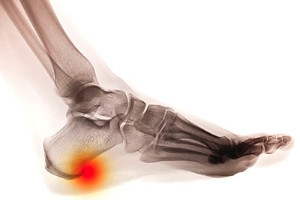

A heel spur is known to be an uncomfortable and painful condition which develops in the heel of the foot and will typically affect the surrounding area. It is a small bony protrusion that grows in between the heel and the arch, and is often referred to as “heel spur syndrome.” If you are afflicted with this condition, there may be strong symptoms indicating its existence, including a sharp pain in the heel, which may be especially prominent in the morning, severe tenderness, or a consistent ache that may often be felt throughout the day. Research has shown that age may play a significant role in the formation of heel spurs and the pads in the heels may wear down as a result of this. This may cause diminished shock absorption in the heel which may cause this ailment to develop. If you would like additional information about heel spurs, a podiatrist can help you with a proper diagnosis and suggest correct treatment options.

Heel spurs are formed by calcium deposits on the back of the foot where the heel is. This can also be caused by small fragments of bone breaking off one section of the foot, attaching onto the back of the foot. Heel spurs can also be bone growth on the back of the foot and may grow in the direction of the arch of the foot.

Older individuals usually suffer from heel spurs and pain sometimes intensifies with age. One of the main condition's spurs are related to is plantar fasciitis.

Pain

The pain associated with spurs is often because of weight placed on the feet. When someone is walking, their entire weight is concentrated on the feet. Bone spurs then have the tendency to affect other bones and tissues around the foot. As the pain continues, the feet will become tender and sensitive over time.

Heel spurs are the result of calcium deposits that cause bony protrusions on the underside of the heel. Heel spurs are usually painless, but they have the potential to cause heel pain. Heel spurs tend to be associated with plantar fasciitis, which is a condition that causes inflammation of the band of connective tissue that runs along the bottom of the foot. They most often occur to athletes whose sports involve a lot of running and jumping.

Some risk factors for developing heel spurs include running and jogging on hard surfaces, being obese, wearing poorly fitting shoes, or having walking gait abnormalities.

It is possible to have a heel spur without showing signs of any symptoms. However, if inflammation develops at the point of the spur’s formation, you may have pain while walking or running. In terms of diagnosis, sometimes all a doctor needs to know is that the patient is experiencing a sharp pain localized to the heel to diagnose a heel spur. Other times, an x-ray may be needed to confirm the presence of a heel spur.

Heel spurs can be prevented by wearing well-fitting shoes that have shock-absorbent soles. You should also be sure that you are choosing the right shoe for the activity you want to partake in; for example, do not wear walking shoes when you want to go on a run. Additionally, maintaining a healthy weight can be beneficial toward preventing heel spurs, as it will prevent an excess amount of pressure being placed on the ligaments.

There are a variety of treatment options for people with heel spurs. Some of these include stretching exercises, physical therapy, shoe inserts, or taping and strapping to rest stressed muscles and tendons. If you have heel pain that lasts longer than a month, don’t hesitate to seek help from a podiatrist. Your doctor can help you determine which treatment option is best for you.